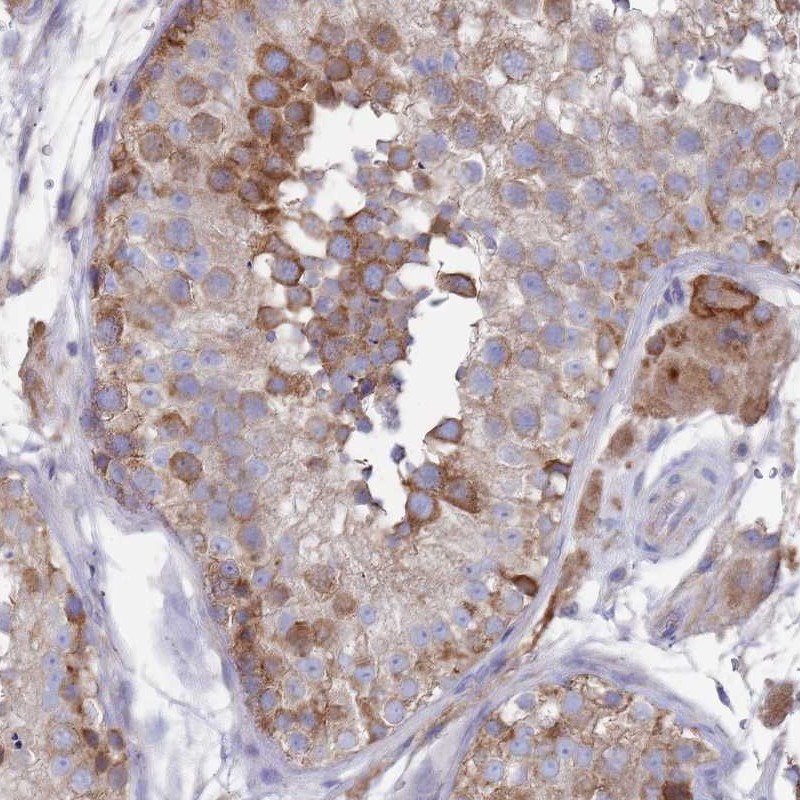

Immunohistochemical staining of human testis shows moderate cytoplasmic/nuclear membranous positivity in cells in seminiferous ducts and cytoplasmic positivity in leydig cells.